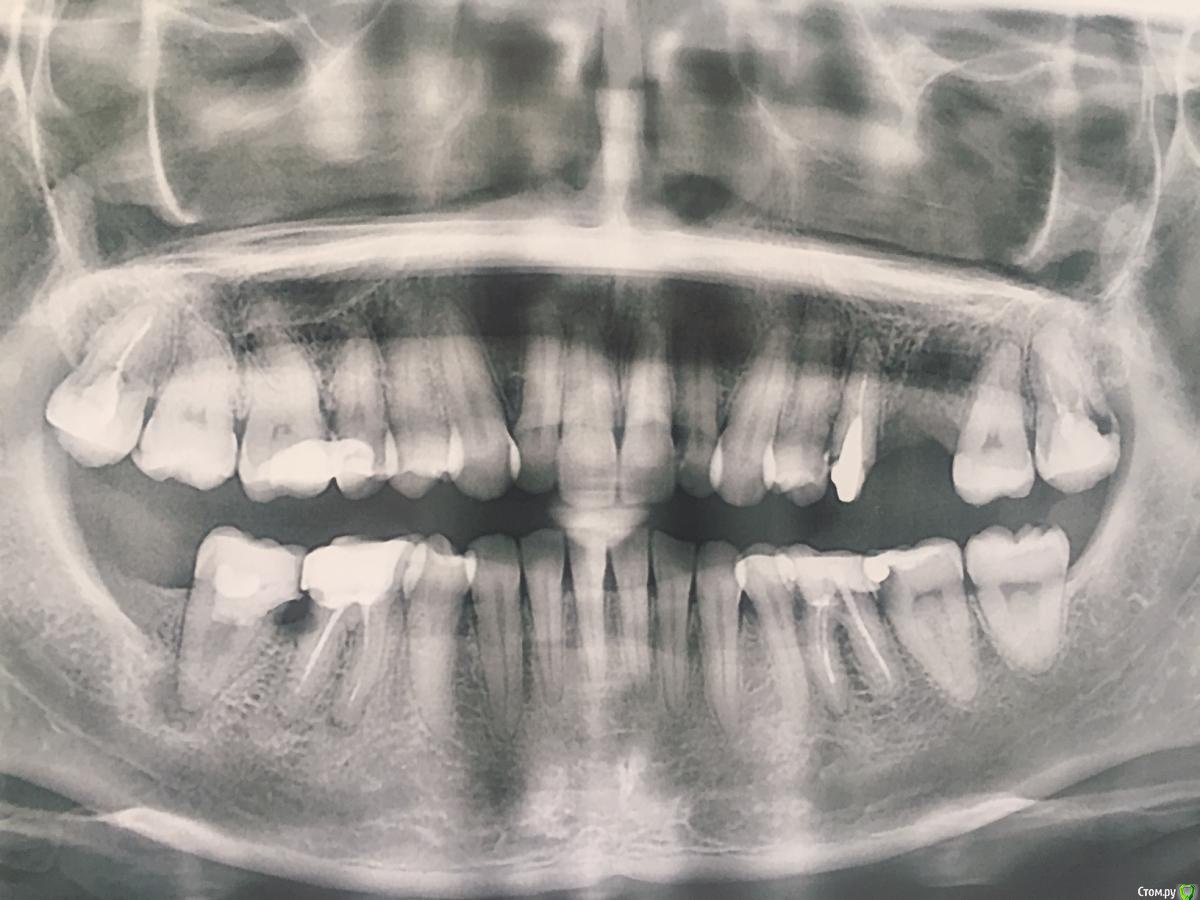

Добрый день. Мне 34 года. С детства дистальный прикус, особо не беспокоило. Незакладка 5 зубов на нижней челюсти. 2 месяца назад из-за кисты, пришлось снять мост и удалить 6 слева на верхней челюсти. Дилемма: вставлять имплант на место 6? Или же передвинуть зубы (на верхней челюсти их гораздо больше)))